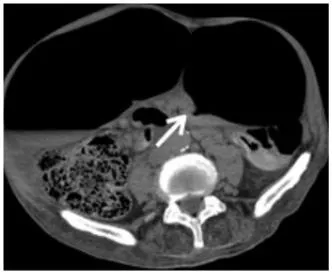

X-marks-the-spot sign : complete obstruction 되면서 distal, proximal sigmoid colon이 둘 다 obstruction 되는데, 이 두 속의 transition point가 반대로 나타나서 마치 x표시 같다.

Split wall sign : incomplete obstruction, partial obstruction시 distal, proximal colon 사이 mesenteric fat이 들어가며 마치 둘을 분리시키는 것 같다

Steel pan sign